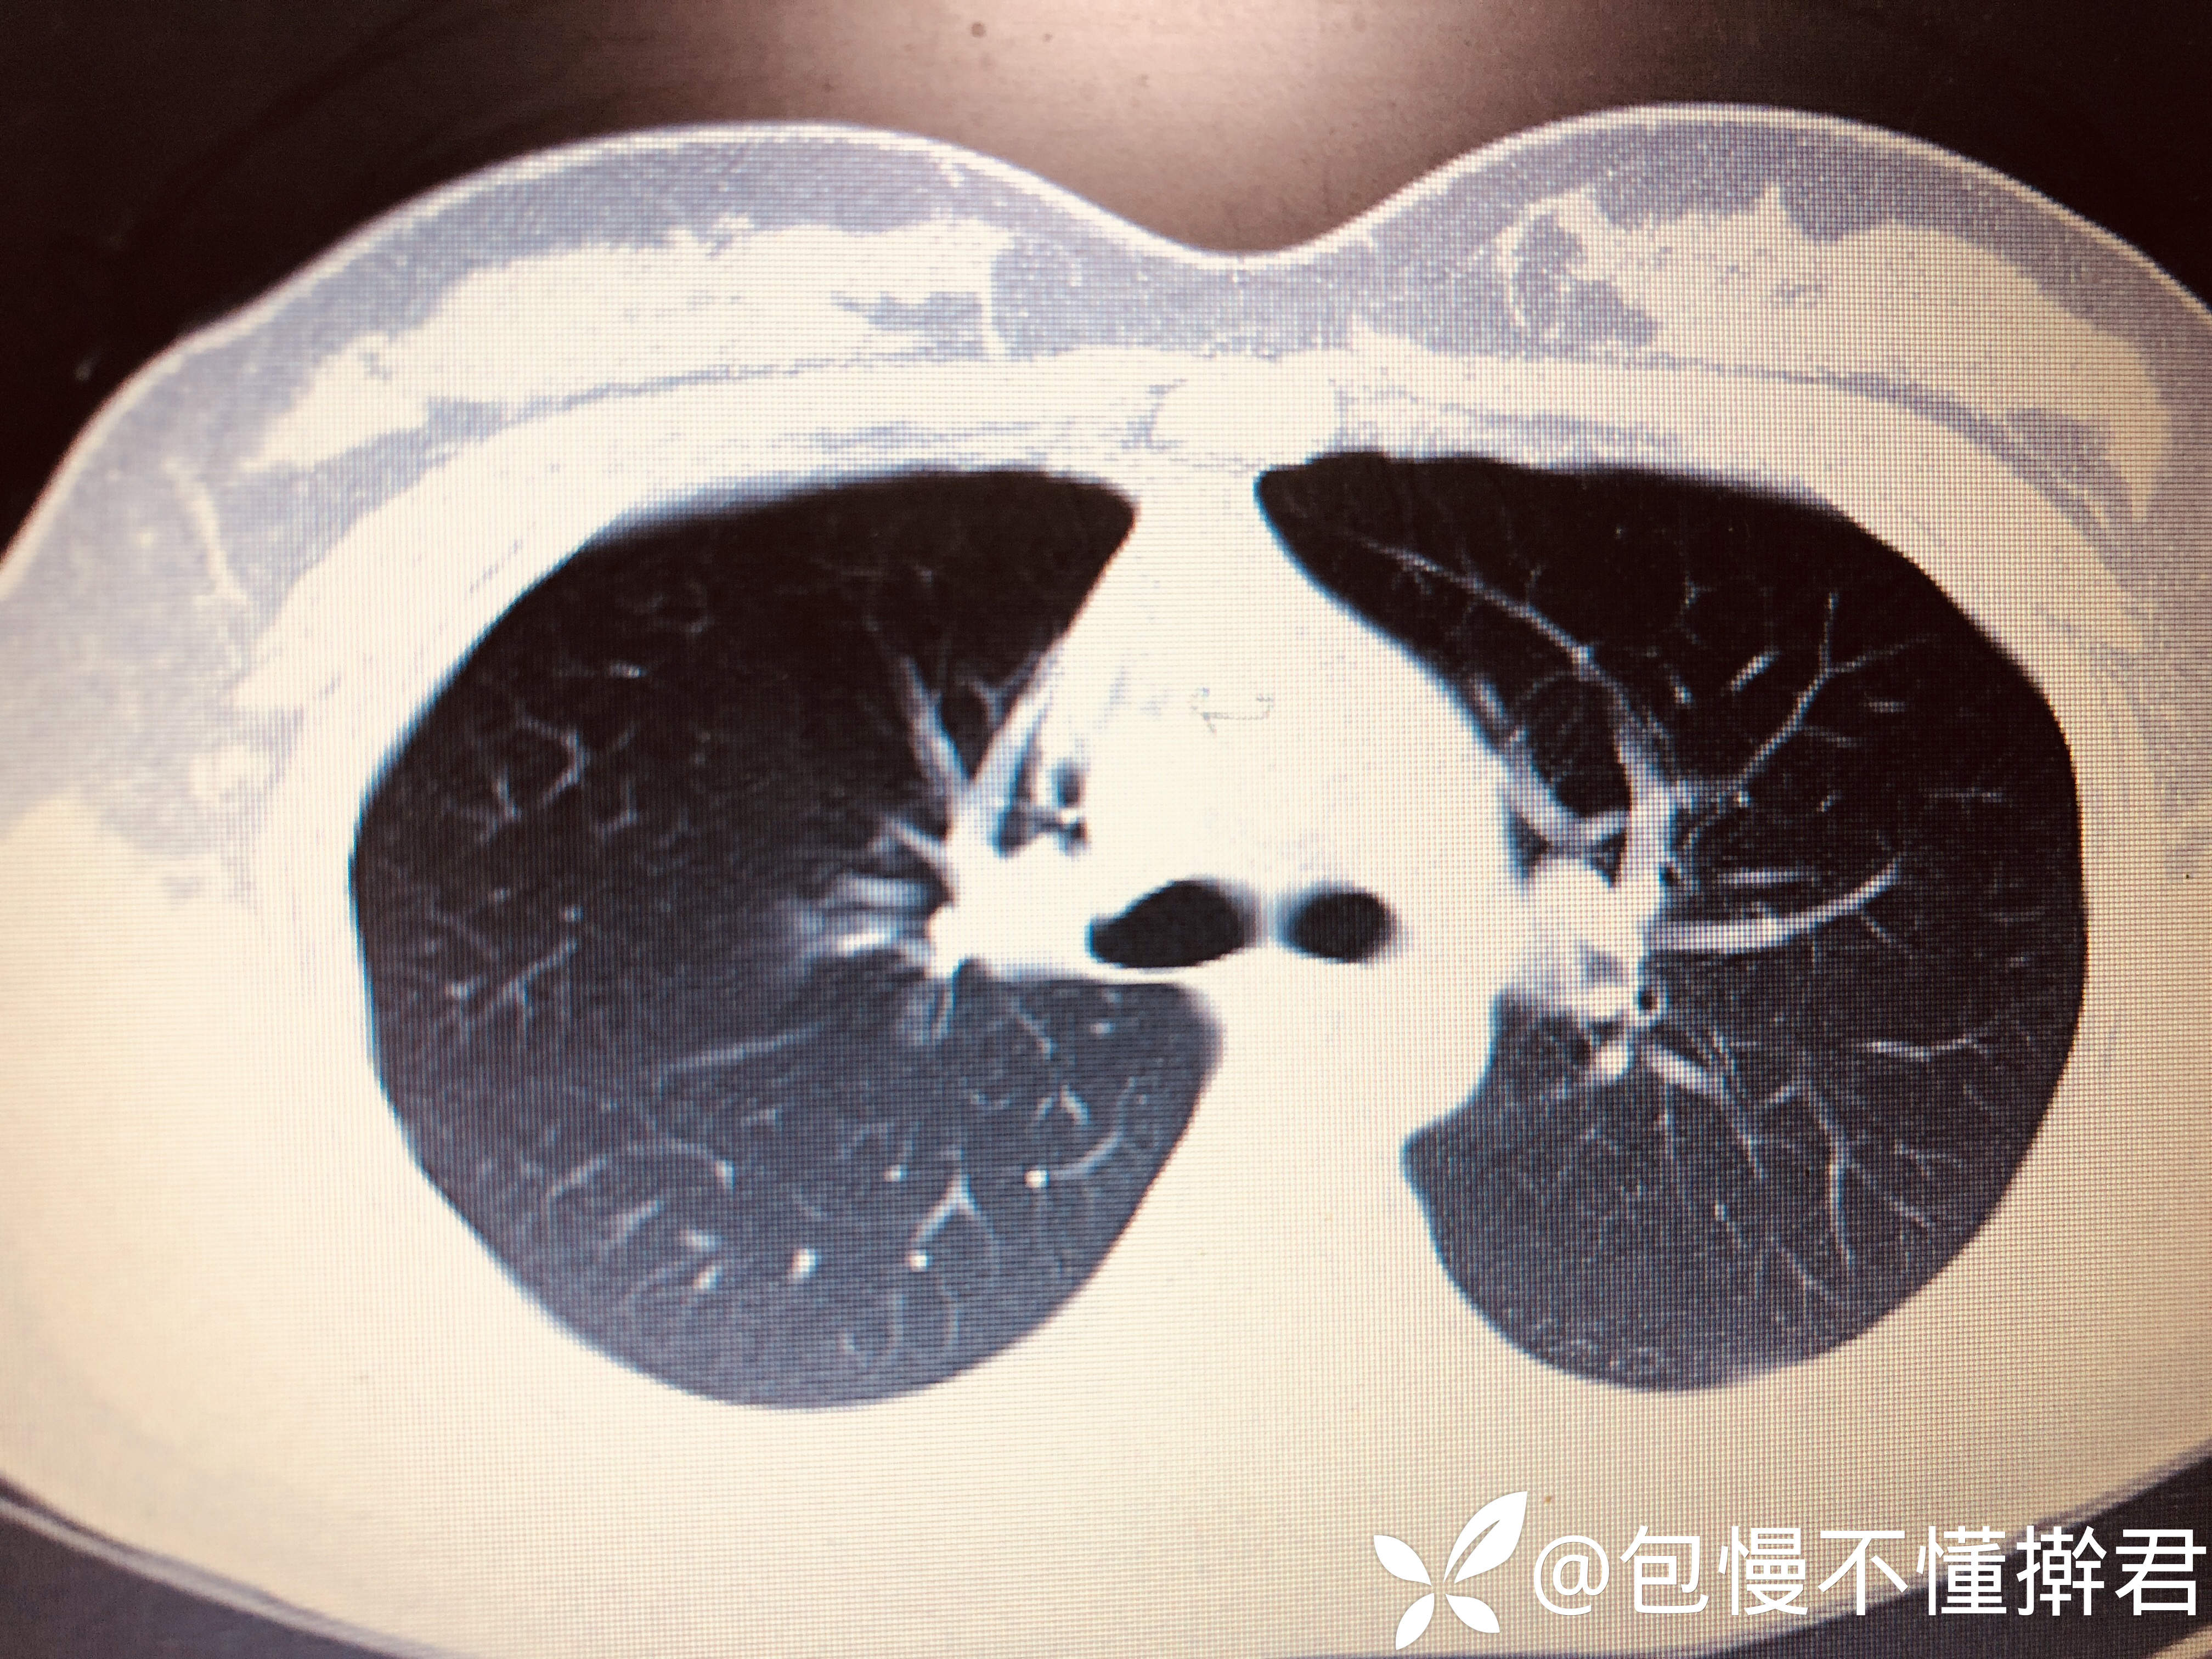

主诉:体检发现右上肺占位5天

简要病史:5天前因入学体检就诊当地医院行胸片右肺上叶不张,无呼吸系统症状

增强CT:

临床诊断:右上肺占位待查